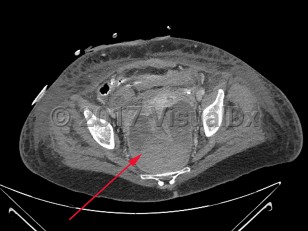

Perirectal abscess

A perirectal abscess is a collection of pus in the perianal area resulting from progression of an infected anal gland.

Perirectal abscesses develop when an anal crypt becomes obstructed, allowing bacterial overgrowth. Complex anorectal abscesses are deeper and classified based on their anatomic location. The American Association for the Surgery of Trauma describes 5 grades of perirectal abscesses: perianal abscess, intersphincteric abscess or ischiorectal abscess, horseshoe abscess, supralevator abscess, and necrotizing soft tissue infection.

The diagnosis is made based on the history and a compatible physical examination. Imaging studies, including computed tomography imaging, may also be helpful.